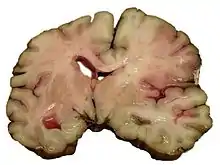

Intracerebral hemorrhage

It generally occurs in small arteries or arterioles and is commonly due to hypertension,[52] intracranial vascular malformations (including cavernous angiomas or arteriovenous malformations), cerebral amyloid angiopathy, or infarcts into which secondary hemorrhage has occurred.[2] Other potential causes are trauma, bleeding disorders, amyloid angiopathy, illicit drug use (e.g., amphetamines or cocaine). The hematoma enlarges until pressure from surrounding tissue limits its growth, or until it decompresses by emptying into the ventricular system, CSF or the pial surface. A third of intracerebral bleed is into the brain's ventricles. ICH has a mortality rate of 44 percent after 30 days, higher than ischemic stroke or subarachnoid hemorrhage (which technically may also be classified as a type of stroke[2]).